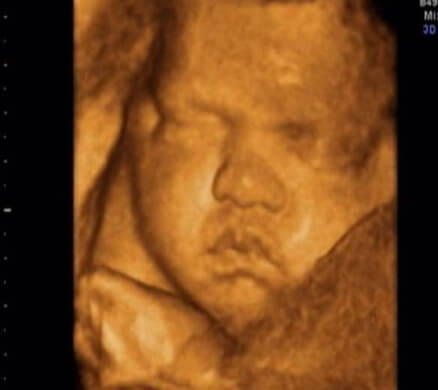

34 Haftalık Bebeğin Ultrason Görüntüsü

• Bebeğinizin ultrason görüntüsünün internette bulduklarınızdan ve başka annelerinkinden farklı olması sizi endişelendirmemelidir; çünkü her bebeğin anne karnındaki duruşu ve hareketleri birbirinden farklıdır.

• 34 haftalık bebeğinizin ultrason görüntüsünde adeta yenidoğan bir bebeğin video kaydını izliyor gibi hissetmeniz doğaldır; çünkü bebeğiniz artık yenidoğan bebeğin yapabildiği neredeyse her şeyi yapabiliyor.

• Bu dönemde annelerin en çok endişelendiği konu bebeklerinin baş aşağı dönmüş olup olmamasıdır; bu dönüş yaklaşık olarak 32 ilâ 38. hafta arasında gerçekleşmektedir.

• Eğer bebeğiniz henüz baş aşağı dönmemişse endişelenmenize gerek yoktur; çünkü bebeklerin büyük çoğunluğu doğum pozisyonunu 38. haftaya kadar almaktadır. Bebeğiniz şu an kendini en rahat hissettiği pozisyonda kalmaya devam ediyor.

• Bebeğinizi, ultrason görüntüsünde, ilk kez baş aşağı gördüyseniz ise erken doğumdan şüphelenmeniz normaldir; ancak korkmayın, 32. hafta baş aşağı dönen bebekler dâhi 40.ya da 41. haftada doğabilmektedir.

34 hafta gebelik ultrason